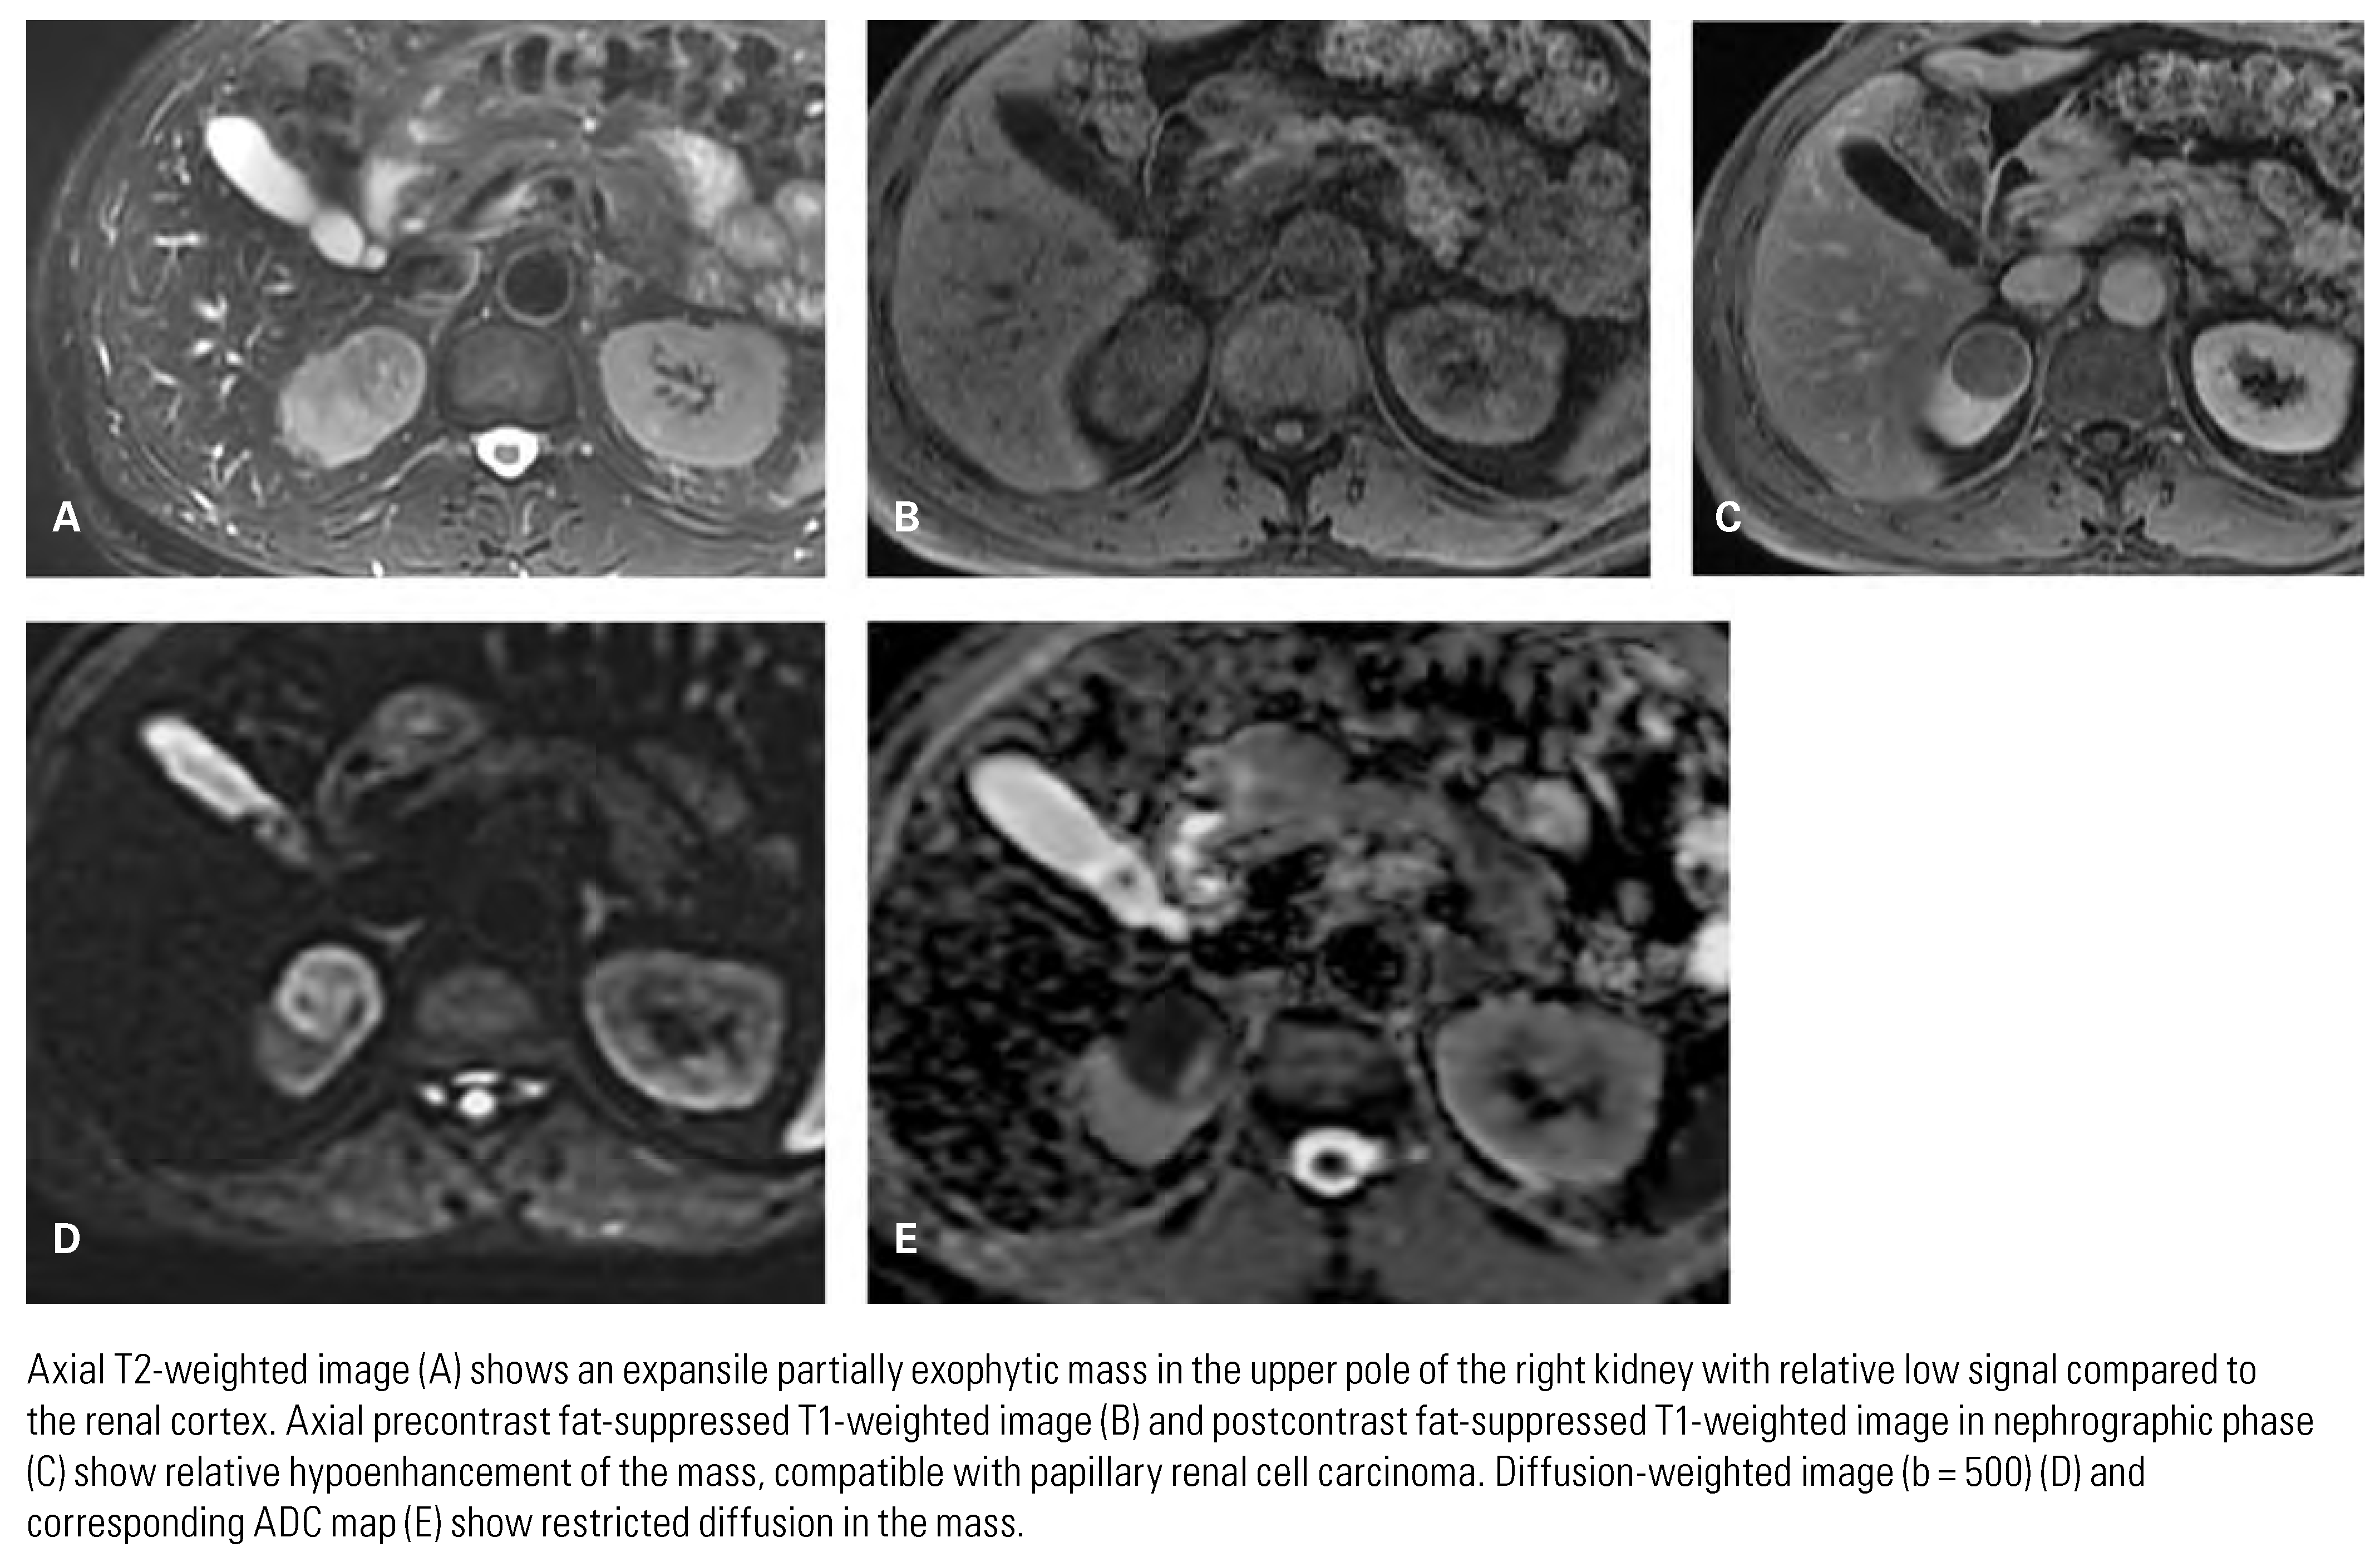

Papillary Renal Cell Carcinoma